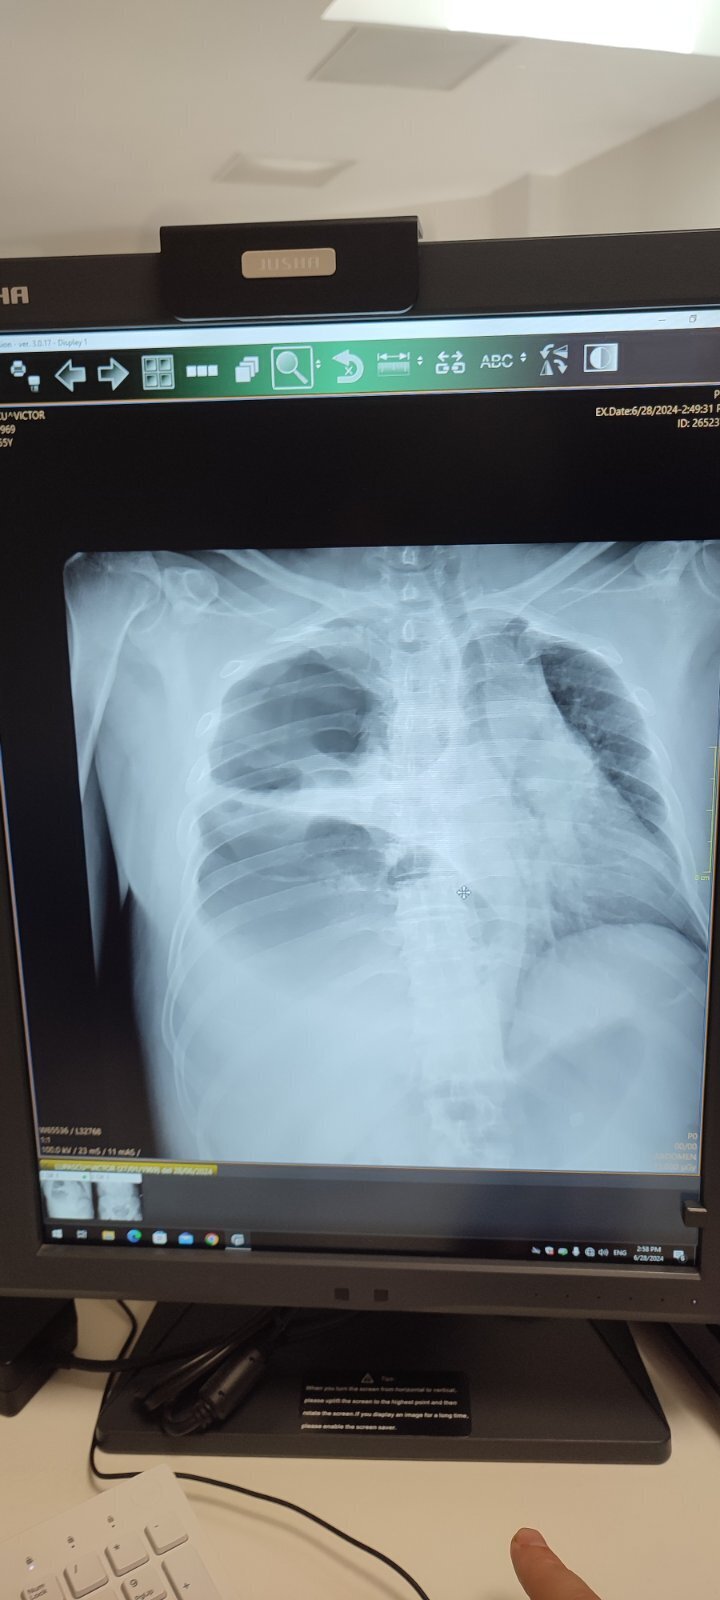

Вот. Если получится что-то понять... Мне тоже скинули, оригинала нет

Иллюстрация к комментарию

Очень похоже на напряжённый пневмоторакс справа с коллабированным правым лёгким (отсутствие лёгочного рисунка справа, смещением средостения влево). Скорее всего есть ещё выпот плевральный справа, тогда получается гидро(серо)пневмоторакс справа.